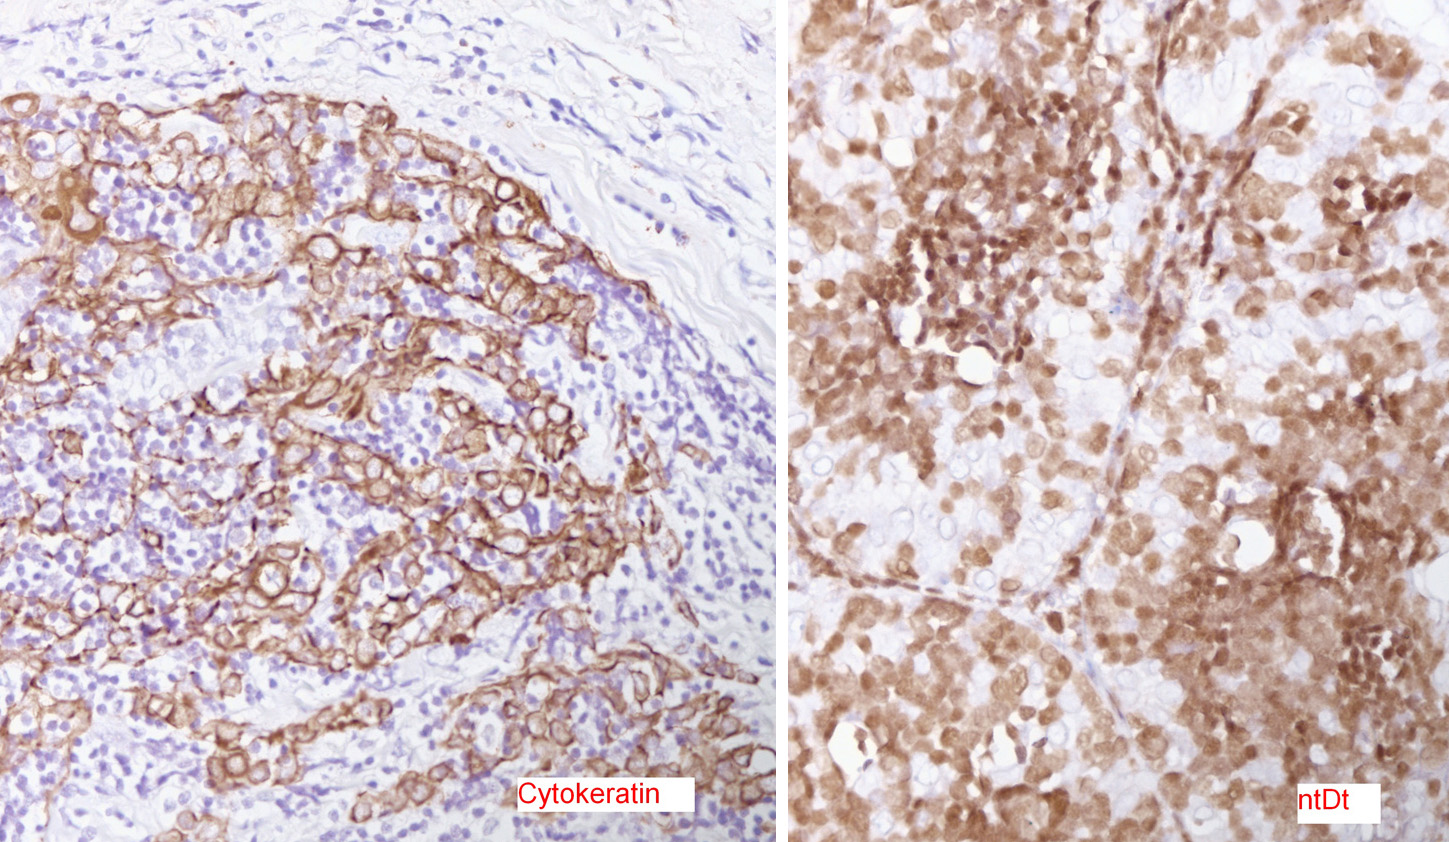

Low power H&E show tumor in below the mesothelial lining. Distinct lobular / organoid appearance noted with two types of cells, small lymphoid cells and large neoplastic cells with clear cytoplasm (bi-phasic pattern). IHC stains showed large cells are cytokeratin positive and small lymphoid cells expressed CD3, CD5 and ntDt (immature thymocytes).

Additional history later revealed a large anterior mediastinal mass with tracheal compression and seeding of pleura. Main tumor was not resectable. Histology (epithelial elements and thymic lymphoid stroma) and IHC stains support an aggressive thymoma, WHO B2, metastatic to pleura. Normal thymic milieu i.e. immature thymocytes often present in metastasis along with neoplastic epithelial component. Metastatic thymoma must be considered in the differential diagnosis with bi -phasic patten as illustrated above.